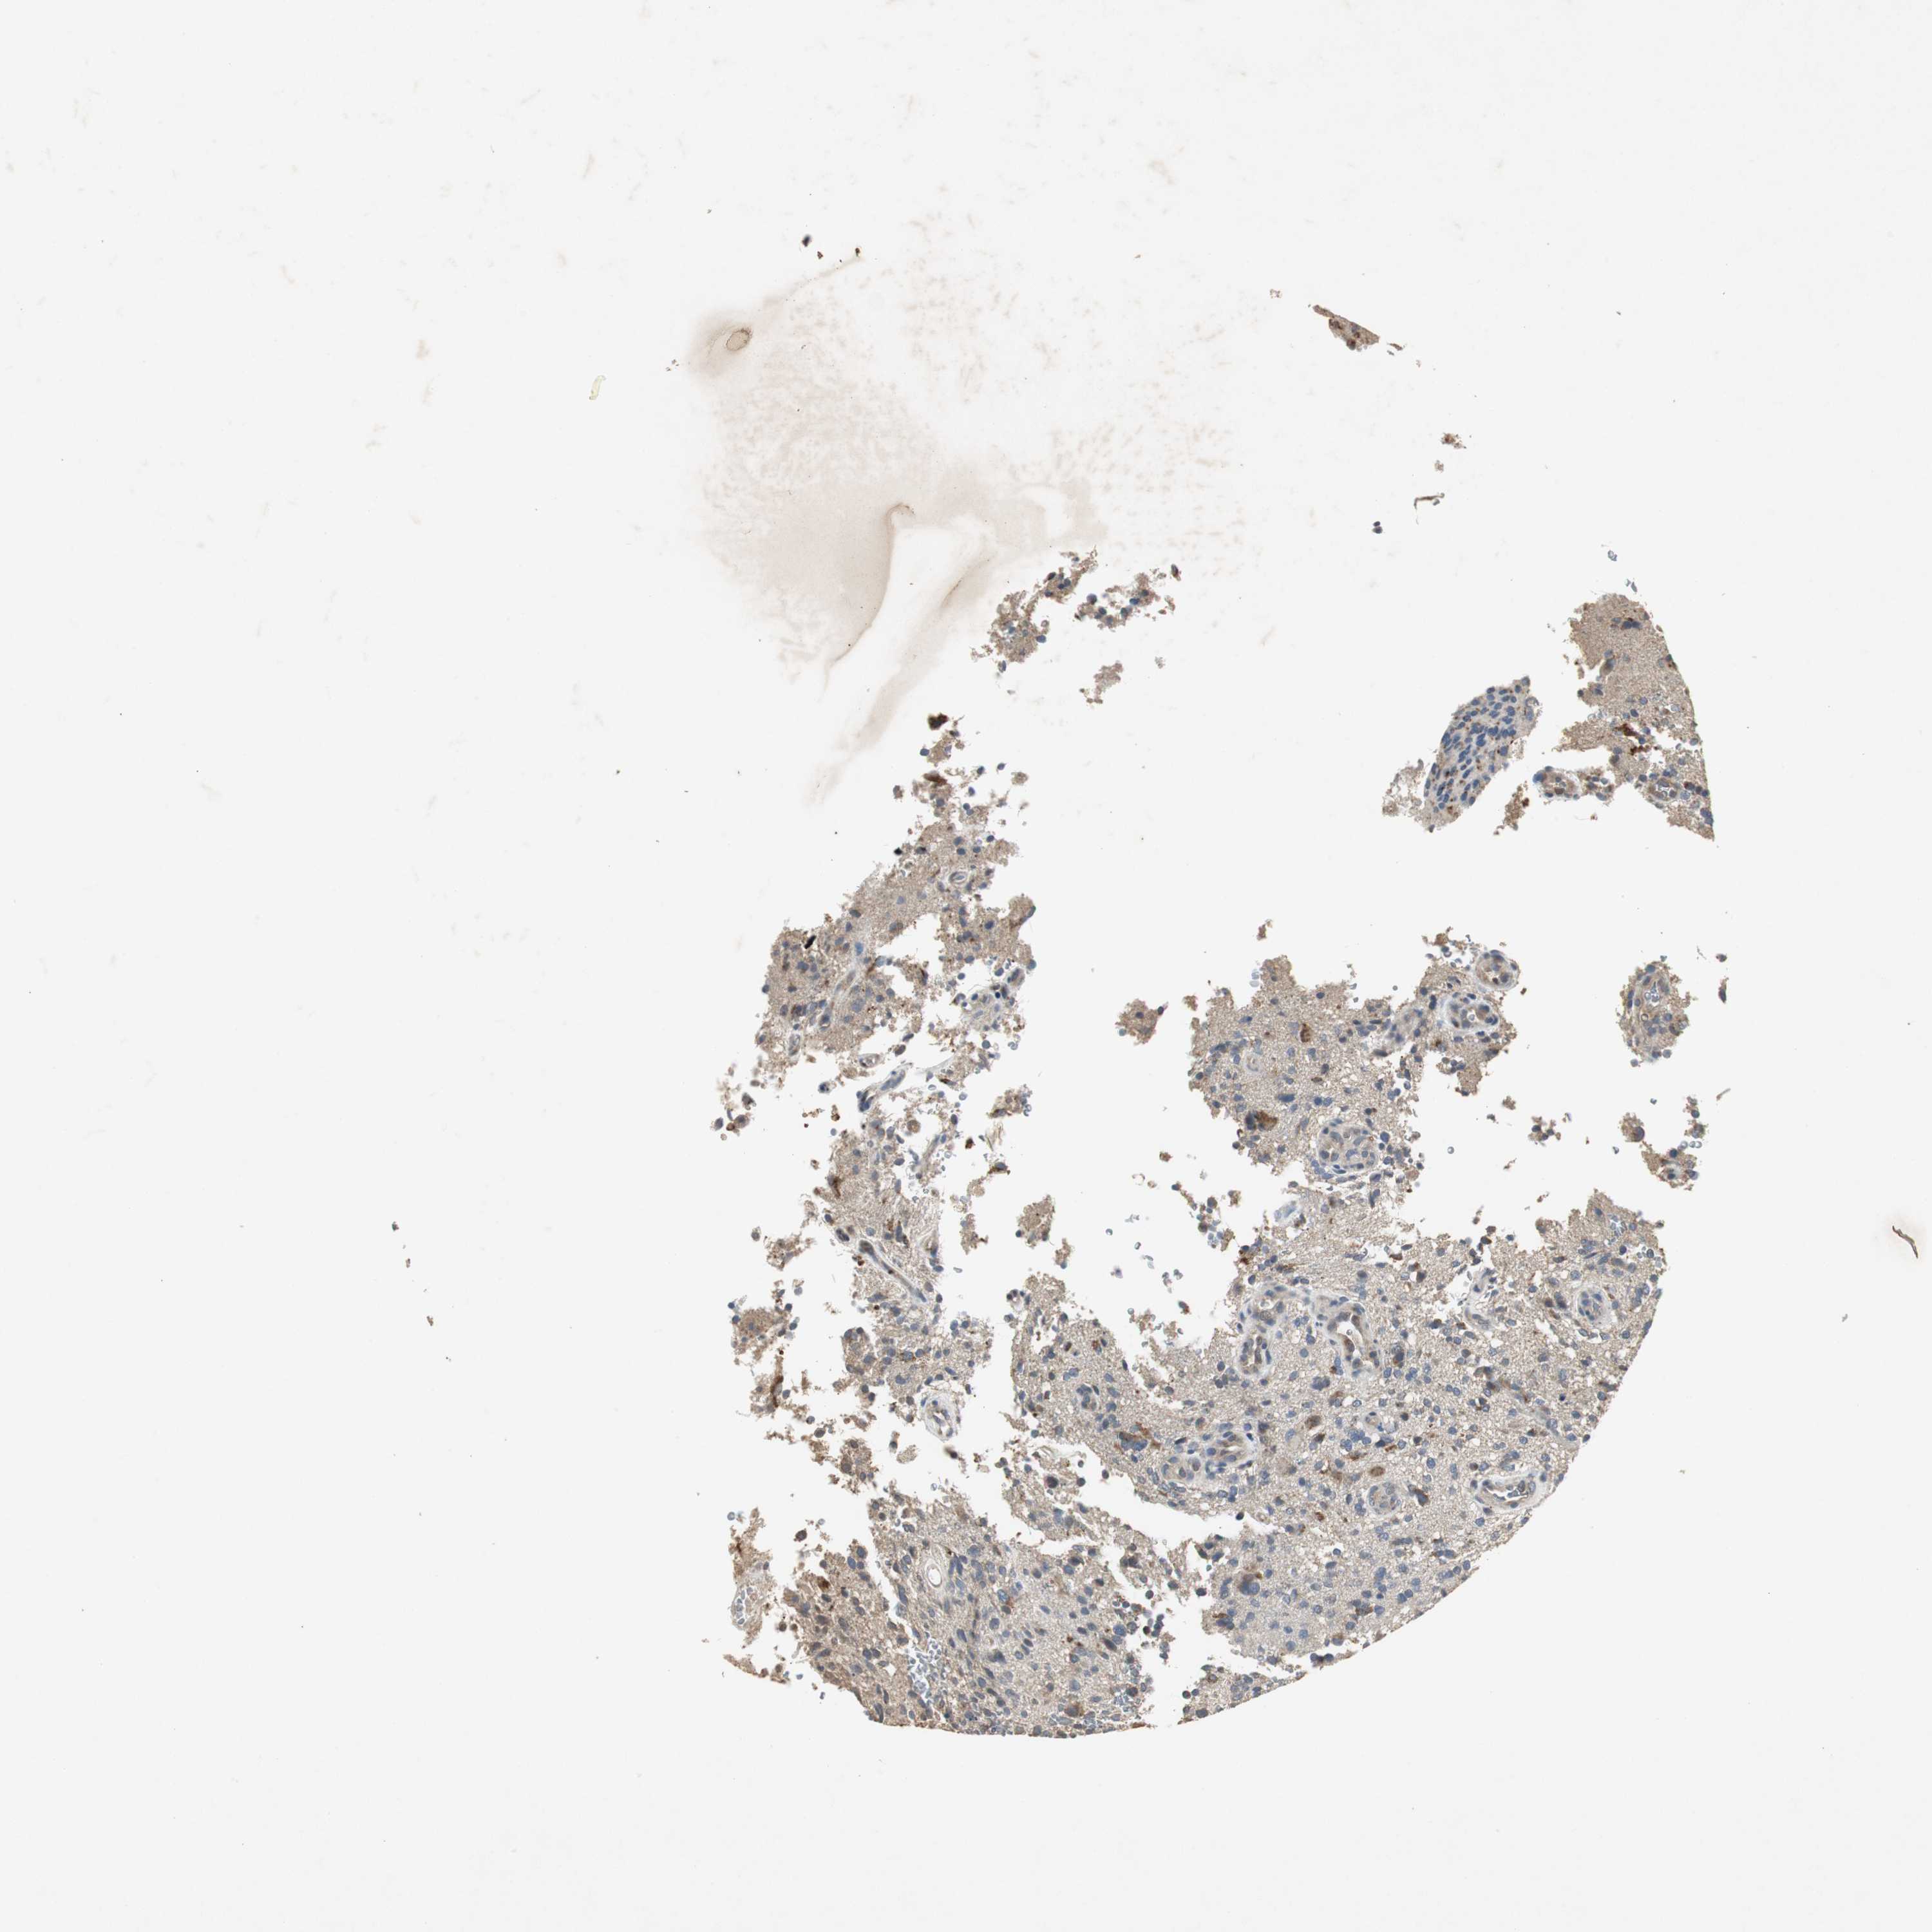

GLIOMA - Protein expressioni

A mouse-over function shows sample information and annotation data. Click on an image to view it in a full screen mode. Samples can be filtered based on level of antibody staining by selecting one or several of the following categories: high, medium, low and not detected. The assay and annotation is described here.

Note that samples used for immunohistochemistry by the Human Protein Atlas do not correspond to samples in the TCGA dataset.

Antibody stainingi

Antibody staining in the annotated cell types in the current human tissue is reported as not detected, low, medium, or high, based on conventional immunohistochemistry profiling in selected tissues. This score is based on the combination of the staining intensity and fraction of stained cells.

Each image is clickable and will lead to virtual microscopy that enables deeper exploration of all samples and also displays staining intensity scores, fraction scores and subcellular localization as well as patient and tissue information for each sample.

Antibody HPA006514

Staining

High

Medium

Low

Not detected

Intensity

Strong

Moderate

Weak

Negative

Quantity

>75%

75%-25%

<25%

None

Location

Nuclear

Cytoplasmic/membranous

Cytoplasmic/membranous,nuclear

Glioma, malignant, High grade

Glioma, malignant, NOS